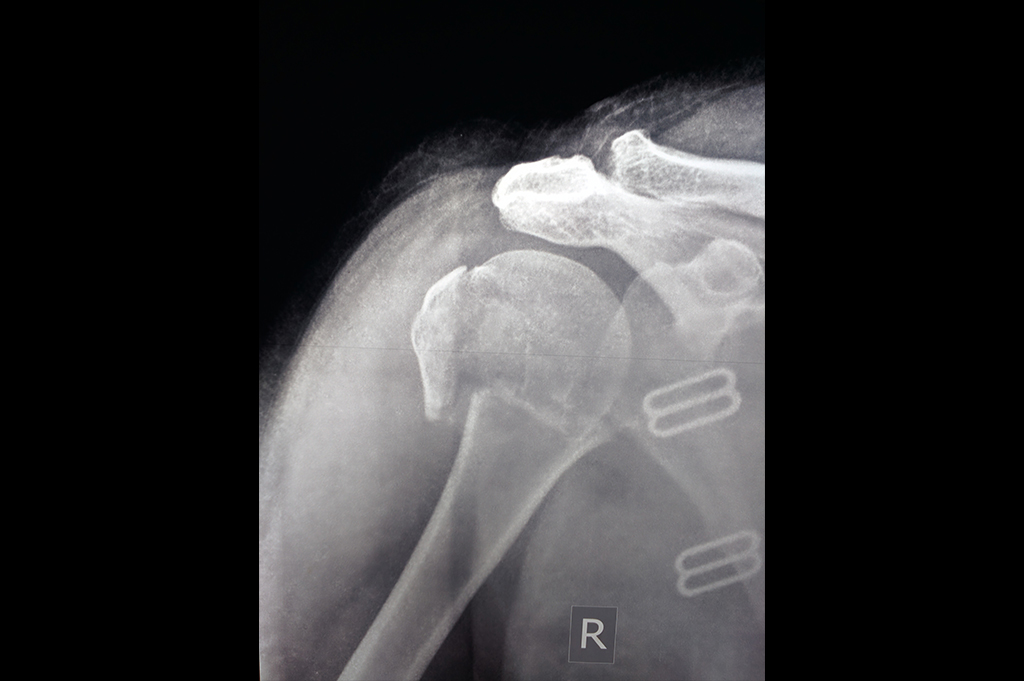

Proximal Humerus